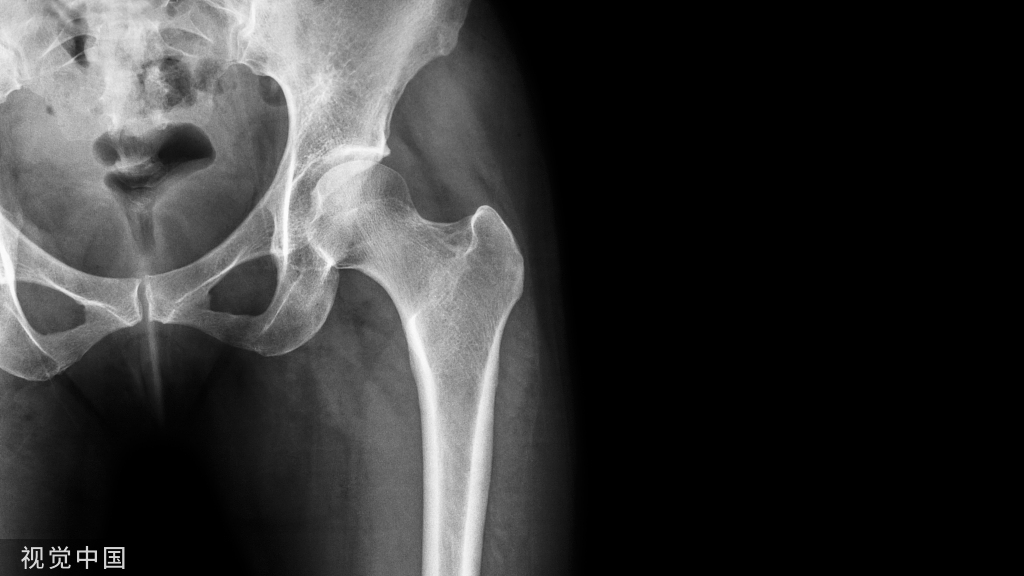

这些药物有助于强化骨骼并防止骨折。骨质疏松症骨折最常见的部位是手腕、臀部和脊柱。髋部骨折会导致生活质量严重下降,甚至会增加死亡风险。

股骨骨折。长期双膦酸盐治疗与一种罕见的股骨转子下骨折有关。这种损伤被称为非典型股骨骨折,类似于应力性骨折,会引起轻微的疼痛并逐渐恶化。如果不及早发现,可能会发生股骨完全骨折。